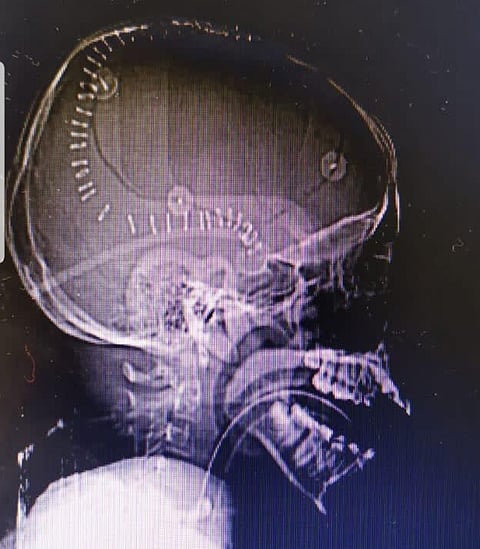

وتفصيلاً؛ أوضح استشاري ورئيس قسم جراحة المخ والأعصاب، قائد الفريق الطبي الدكتور زهير هوساوي، أن المريض حضر لقسم الطوارئ والحوادث وهو يعاني إصابة مباشرة في الدماغ وفقدان الوعي كاملاً إثر حادث مروري وبعد إجراء الفحوصات والأشعة اللازمة تبين وجود نزيف سطحي مع ضغط على جذع الدماغ مع بوادر الوفاة الدماغية؛ وعلى أثر ذلك تم تجهيز المريض في قسم الطوارئ إلى غرفة العمليات خلال ١٥ دقيقة.

وأجريت العملية للمريض بمشاركة الفريق الطبي المكون من الدكتور محمد المشد جراح مخ وأعصاب، والدكتور هاني محبوب أخصائي جراحة مخ وأعصاب والدكتور عبدالرحمن الصائغ طبيب جراحة المخ والأعصاب والدكتور علي الغامدي استشاري تخدير؛ حيث تمت إزالة النزيف عن طريق المايكروسكوب الجراحي والمحافظة على أنسجة الدماغ بتقنية التبريد الدماغي خلال العملية التي استغرقت ساعتين، وتمت مرافقة المريض في العناية المركزة لمدة ٢٤ ساعة وبعد إجراء العملية بثلاثة أيام خرج المريض من المستشفى وهو بصحة جيدة، ولله الحمد.